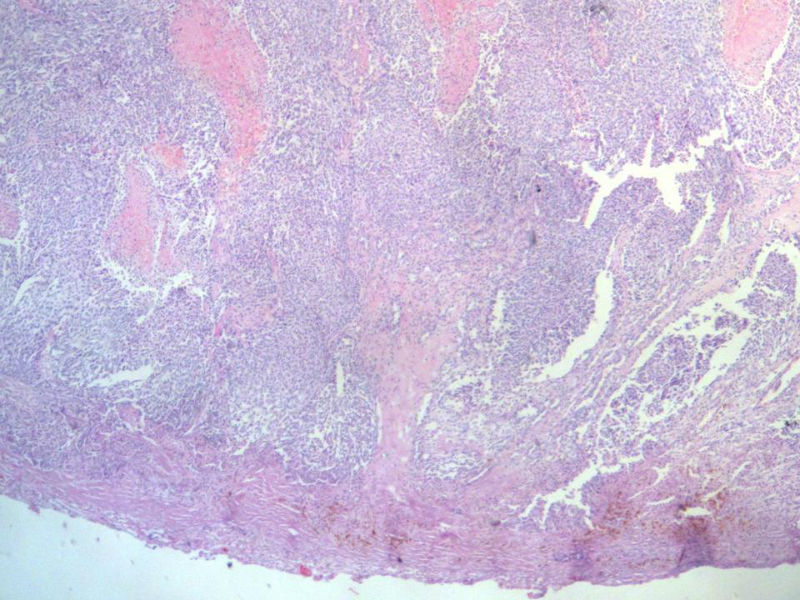

女,64岁,头晕半月,CT检查颅内左颞叶占位,侵犯颅骨和颞肌,手术切除肿物。肉眼,灰白色结节状肿物,3X3X2厘米,边界不清,切面灰黄色,质软。

特别提示:手术前曾做过介入肿瘤栓塞。镜下核分裂15/HP。脑左颞部占位图1

梭形细胞与上皮样漩涡状结构,富于细胞,见个别沙砾体,并见肿瘤性坏死。颅骨及其横纹肌等软组织内见肿瘤呈侵袭性生长。但细胞异型性不是很大。鉴别:

1)恶性脑膜瘤

2)非典型性脑膜瘤

由于非典型性脑膜瘤也可以发生地图状坏死,甚至侵袭性生长。需要计数核分裂数/10HPF,以资鉴别诊断。